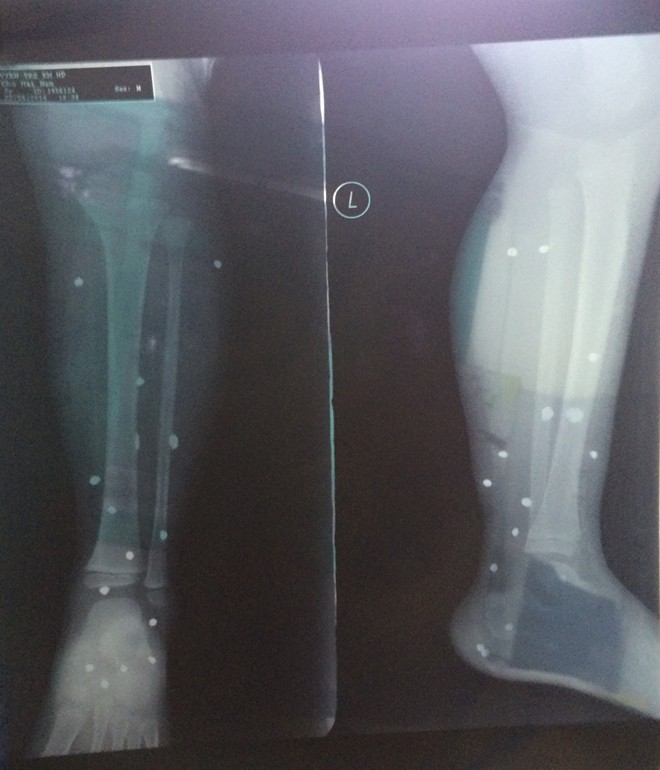

Hình ảnh chụp X-quang các thương tích của bé Nam.

Chẩn đoán bé Nam bị đa vết thương vùng cẳng bàn chân trái. Hình ảnh chụp X-quang cho thấy, trong vùng cẳng chân của bé Nam có khoảng 15 viên đạn, kích thước khoảng 0,5cm. Các bác sỹ xác định, bé Nam bị thương do súng bắn đạn đạn hoa cải. Hiện bé Nam đã được chuyển lên viện Nhi Trung ương để tiếp tục điều trị.